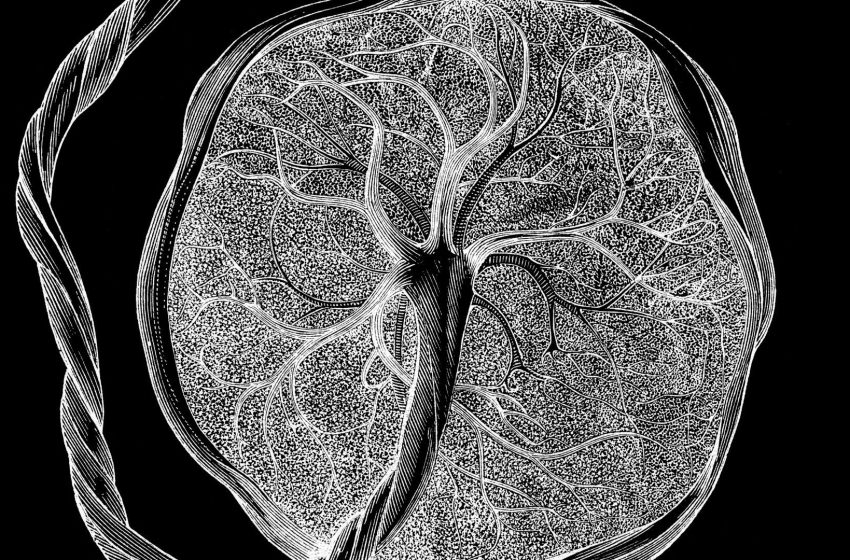

Scientists have unveiled a detailed “atlas” of the placenta and uterus, showing how these unique tissues grow and evolve throughout pregnancy to accommodate a developing fetus.

Li’s lab analyzes tissues in great detail, at the resolution of single cells, with placental development being one of the team’s major research focuses. Their new atlas incorporates snapshots of which genes were active and which proteins were present in the analyzed cells at a given stage of pregnancy. It also looks at “chromatin accessibility,” which reflects how DNA molecules are packaged within the cell and which genes can be activated at a given moment.

In total, the team analyzed about 1.2 million placental and uterine cells, including 200,000 isolated cells and 1 million cells embedded in their original locations within the tissue.